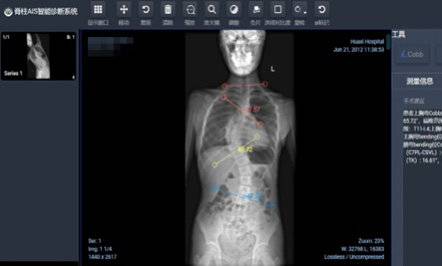

脊柱侧弯诊断系统界面

而在诊断阶段,智能系统还是医生的好助手。范计朋解释,在传统流程中,若要诊断脊柱侧弯,医生需要用尺子测量脊柱的Cobb角度,但这样耗费时间不说,不同医生手工测量时多少会产生一些误差,经验较浅的医生对于大曲度的侧弯可能还需要进行会诊,诊断时间也会因此延长,但经过深度学习后的人工智能系统则能在3~5秒内准确地完成读片、测量,并给出诊断建议。